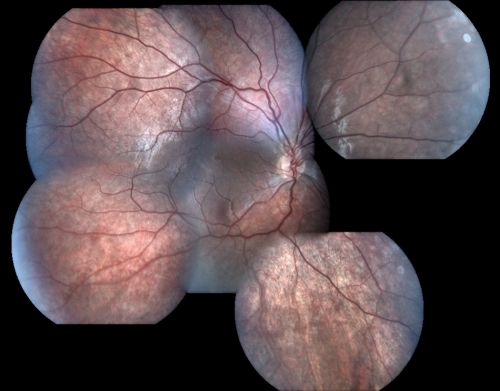

X-Linked Juvenille Retinoschisis 10 Year Old Child treated with Trusopt

10-year-old child has x-linked juvenile retinoschisis VA 20/60, OS is 20/100. Macula and Vision improved with Trusopt drops.